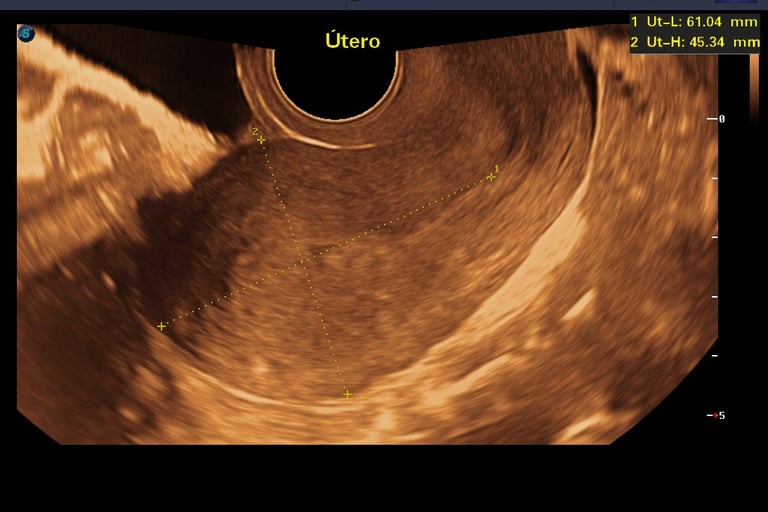

3.- Ultrasonido Pélvico Endovaginal

( o Abdominal)

La revisión ginecológica más precisa para tu útero y ovarios es por vía Endovaginal.

Al ser vía interna, obtenemos una imagen de alta resolución que un ultrasonido externo no puede dar. Fundamental para tu salud íntima.